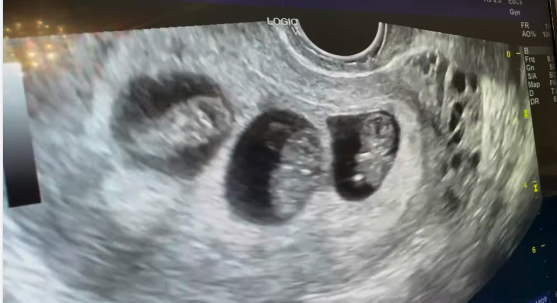

حالات نجاح 2023 3 قلوب صغيرة تنبض 24 فبراير 2021 3 قلوب صغيرة تنبضتنبض بالحياةتنبض بالفرحةو السعادة… المزيد ًتوأم جميل لمريضة عزيزة علينا جدا 19 فبراير 2021 ربنا أكرمها و أكرمنا بها وتم الحمل… المزيد من المنيا وأهل المنيا الكرام 18 فبراير 2021 توأم جميل بعد تأخر حمل 10 سنوات… المزيد ولادة وسط الأمطار 16 فبراير 2021 في الجو الجميل ده (أيوة مفيش أحلي… المزيد صالح 10 فبراير 2021 صالح ولادة طبيعية صباحية جميلة.. والطبيعي يكسب صباح… المزيد حمل طبيعي بعد 4 سنوات تأخر حمل 28 يناير 2021 الحمد لله حمداً مباركاً حمل طبيعي بعد… المزيد تأخر حمل 7 سنوات 20 يناير 2021 تأخر حمل 7 سنواتتكيسات شديده جداًاضطرابات في… المزيد سيلفيا و سيلينا 10 يناير 2021 سيلفيا و سيليناأحدث إنتاجاتنا بتوفيق من ربنا أطفالنا… المزيد المزيد من حالات النجاح